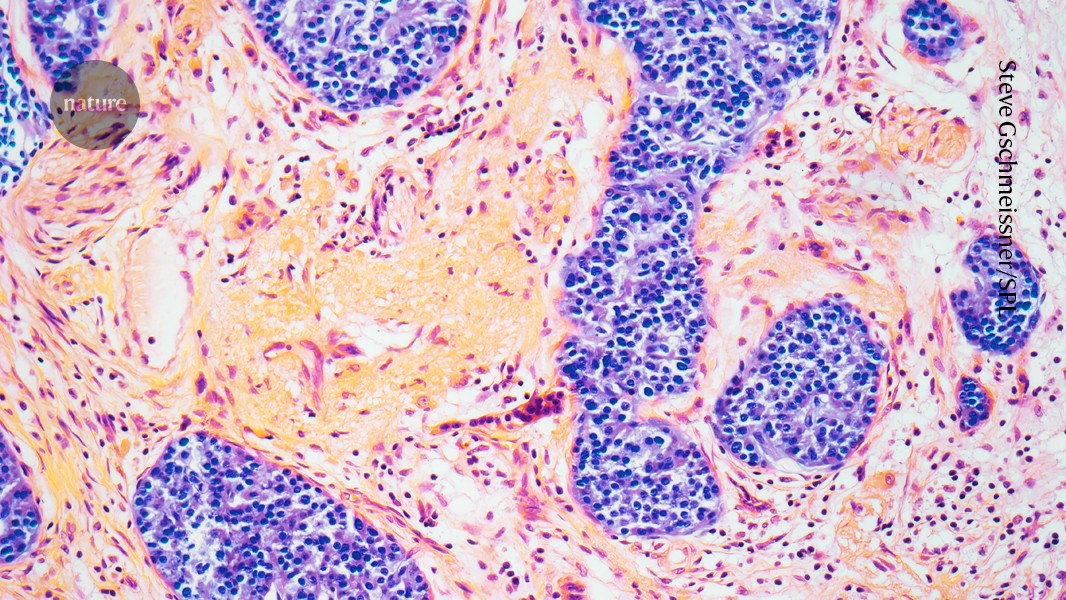

The condition called pancreatitis causes inflammation of the pancreatic tissue (pictured). Credit: Steve Gschmeissner/Science Photo Library